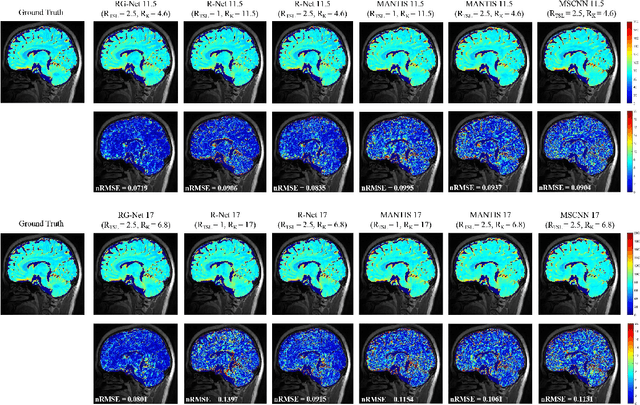

Abstract:Purpose: To propose a novel deep learning-based method called RG-Net (reconstruction and generation network) for highly accelerated MR parametric mapping by undersampling k-space and reducing the acquired contrast number simultaneously. Methods: The proposed framework consists of a reconstruction module and a generative module. The reconstruction module reconstructs MR images from the acquired few undersampled k-space data with the help of a data prior. The generative module then synthesizes the remaining multi-contrast images from the reconstructed images, where the exponential model is implicitly incorporated into the image generation through the supervision of fully sampled labels. The RG-Net was evaluated on the T1\r{ho} mapping data of knee and brain at different acceleration rates. Regional T1\r{ho} analysis for cartilage and the brain was performed to access the performance of RG-Net. Results: RG-Net yields a high-quality T1\r{ho} map at a high acceleration rate of 17. Compared with the competing methods that only undersample k-space, our framework achieves better performance in T1\r{ho} value analysis. Our method also improves quality of T1\r{ho} maps on patient with glioma. Conclusion: The proposed RG-Net that adopted a new strategy by undersampling k-space and reducing the contrast number simultaneously for fast MR parametric mapping, can achieve a high acceleration rate while maintaining good reconstruction quality. The generative module of our framework can also be used as an insert module in other fast MR parametric mapping methods. Keywords: Deep learning, convolutional neural network, fast MR parametric mapping